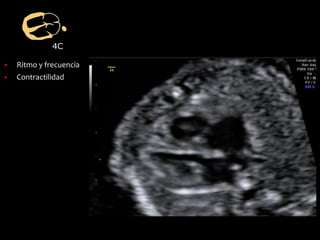

▪ Ritmo y frecuencia

▪ Contractilidad

4C